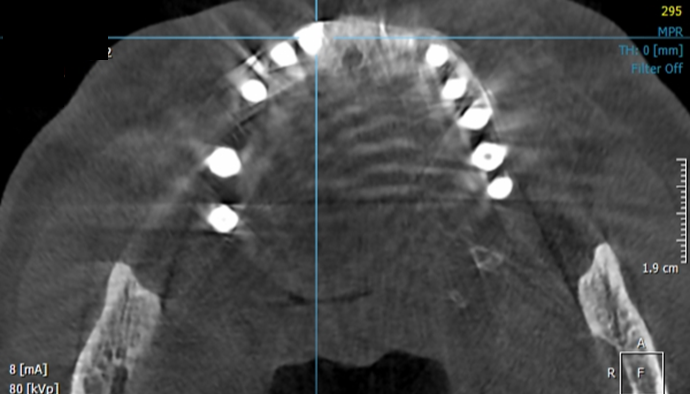

Clinical case: Peri-implantitis treatment case using titanium or NiTi brush

- Courtesy of Dr. Dae-Hee Lee, South Korea -

Dr. Dae-Hee Lee,Maxillary Anterior,Peri-implantitis,Bone regeneration,Aesthetic zone,#21,#22,GBR,Titanium Brush Set